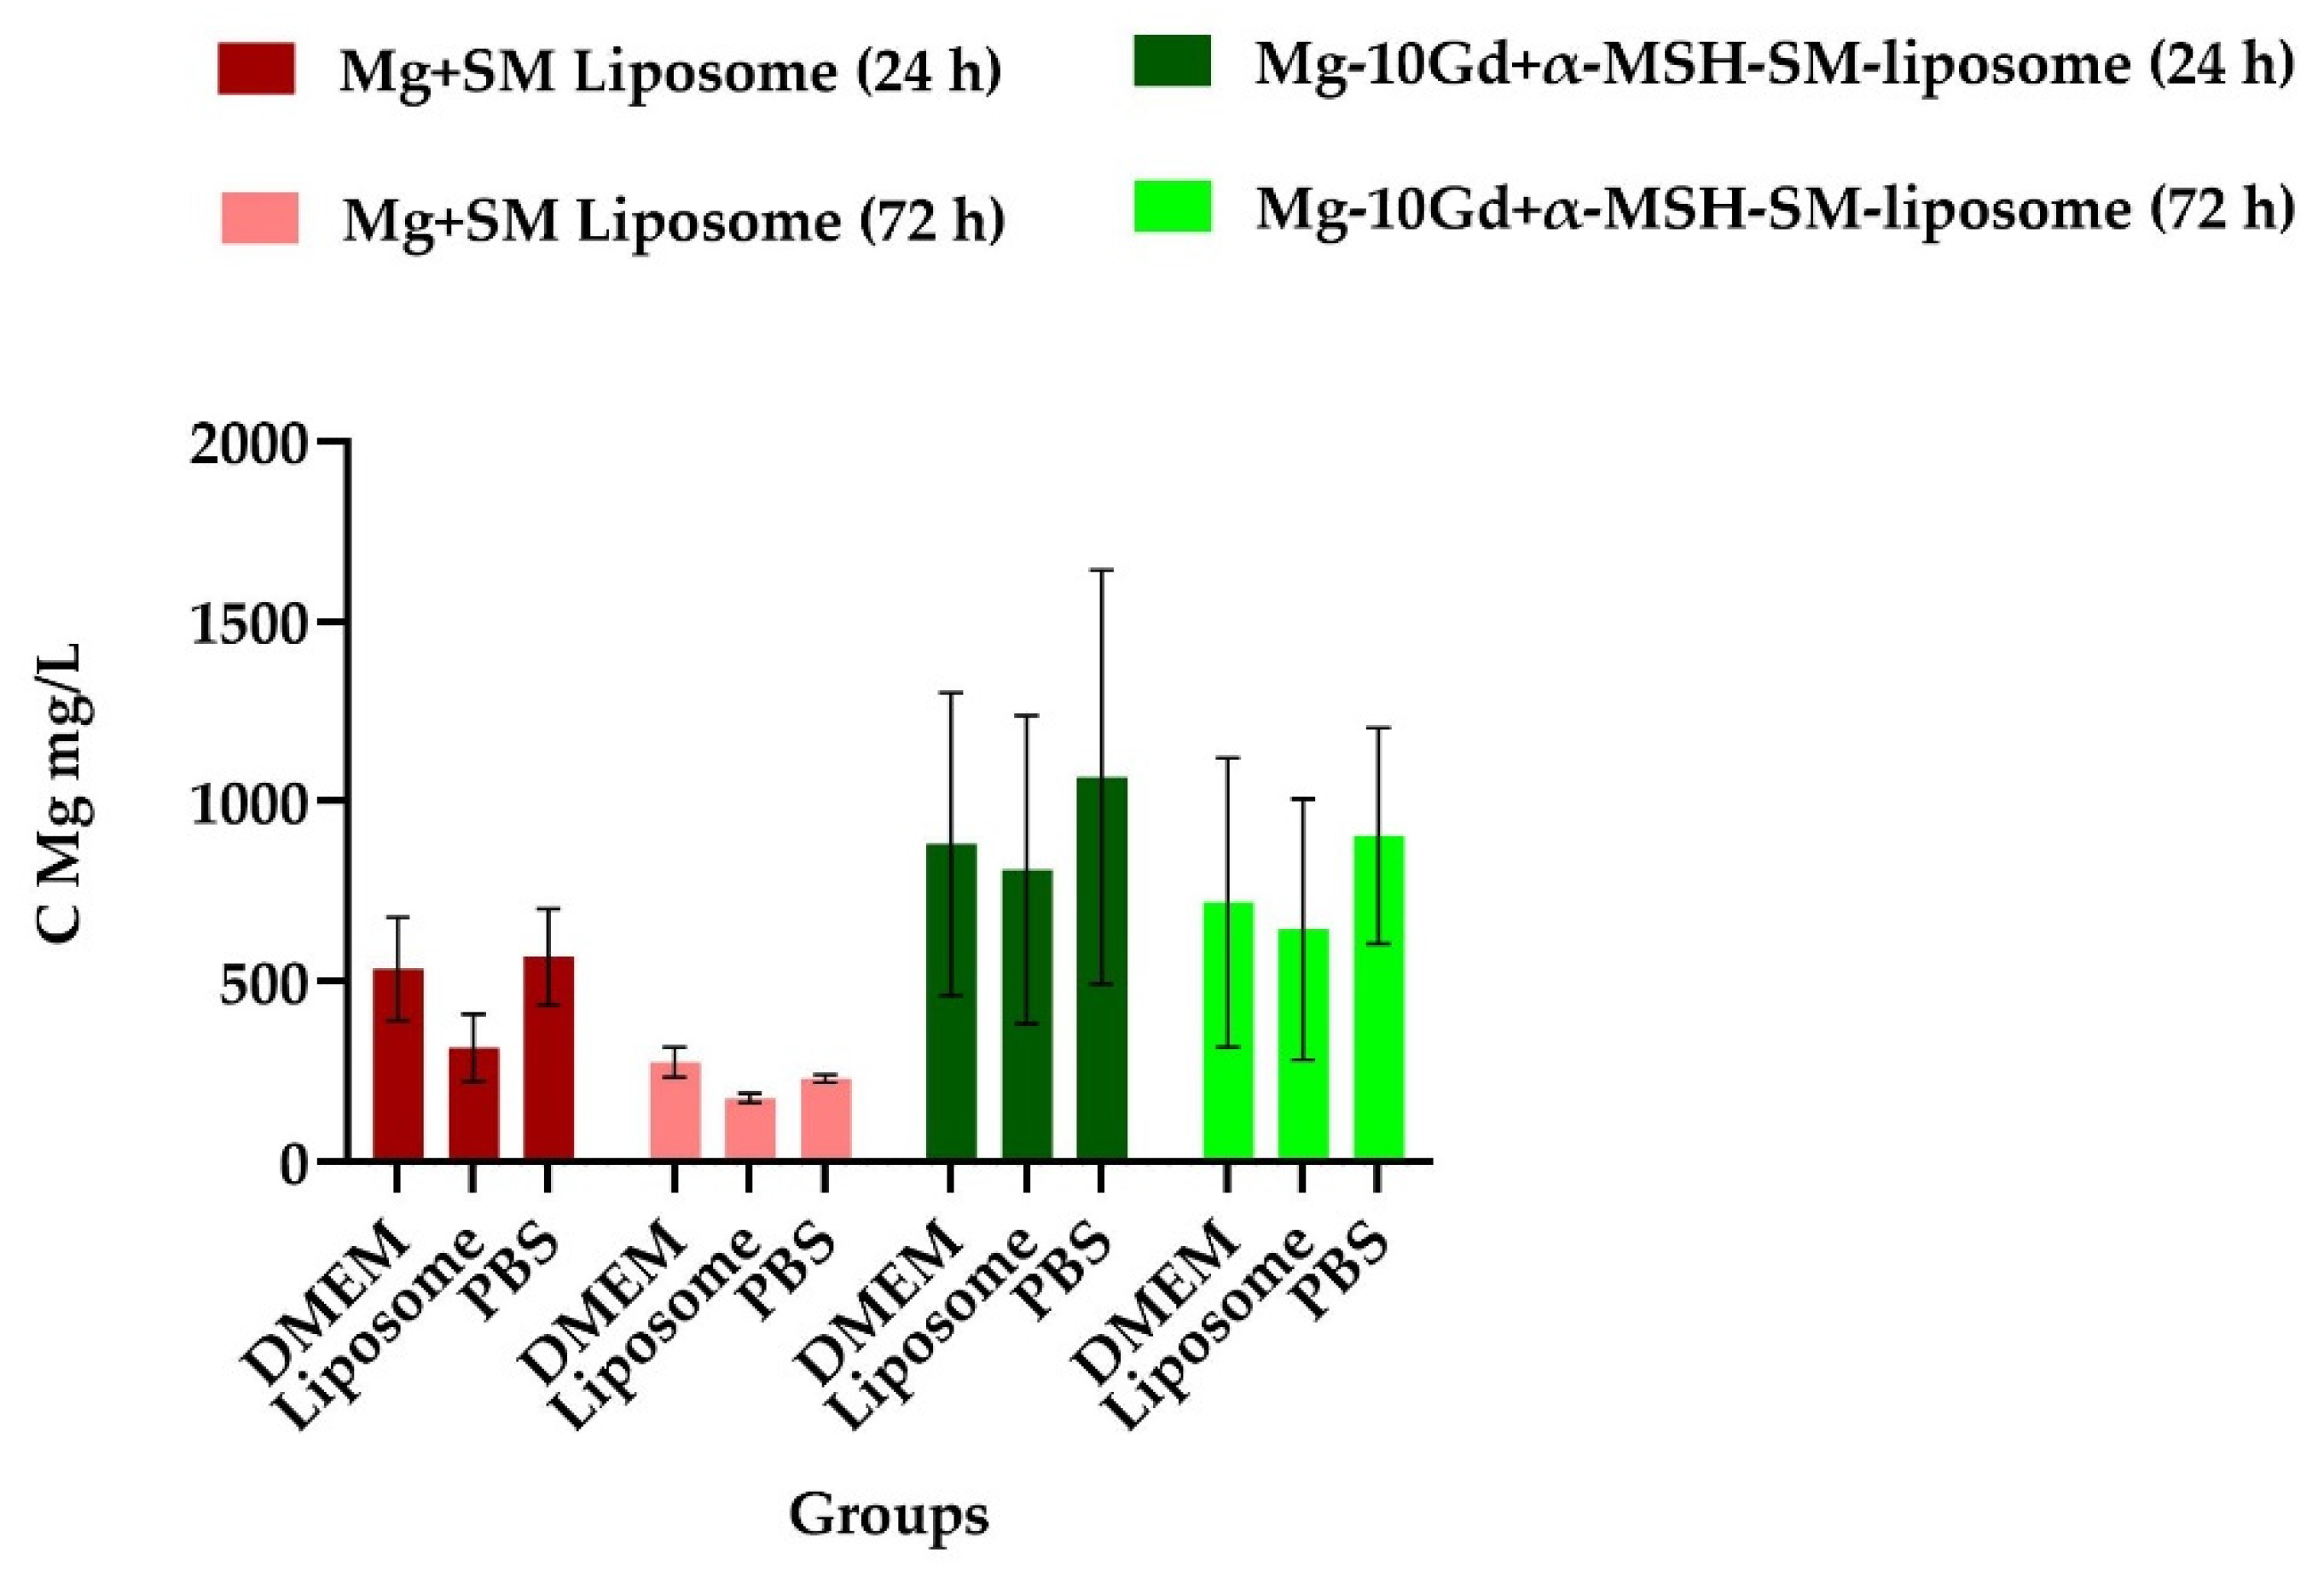

2.1.2. Liposome Effect on Degradation of Mg

4.3.2. Liposome Effect on Degradation of Mg